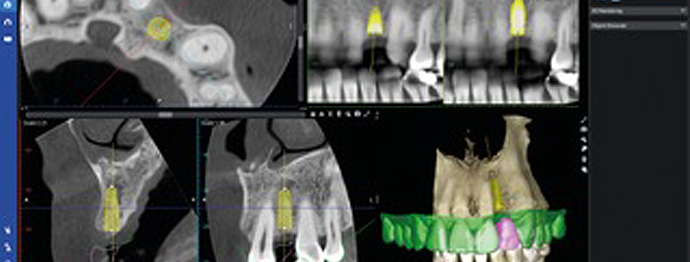

service 09

インプラント治療

天然歯と変わらない

快適な噛み心地

失ってしまった歯は、インプラント治療で快適な状態へ戻すことができます。

当院のインプラント治療では、正確な手術によって自分の歯とほとんど変わらない噛み心地を再現します。

-

より正確に治療ができる

手術用サージカルガイドほんの少しのずれが大きく影響してしまうインプラント治療ですが、サージカルガイドを使うことでコンピュータで設計した位置に高い精度でインプラントを埋入することができます。

-

きちんとした検査のもと

丁寧なご説明事前に検査や治療のシミュレーションをおこない、医師が丁寧に治療内容をご説明します。ご納得いただいたうえで治療に進むので、安心して治療を受けていただけます。